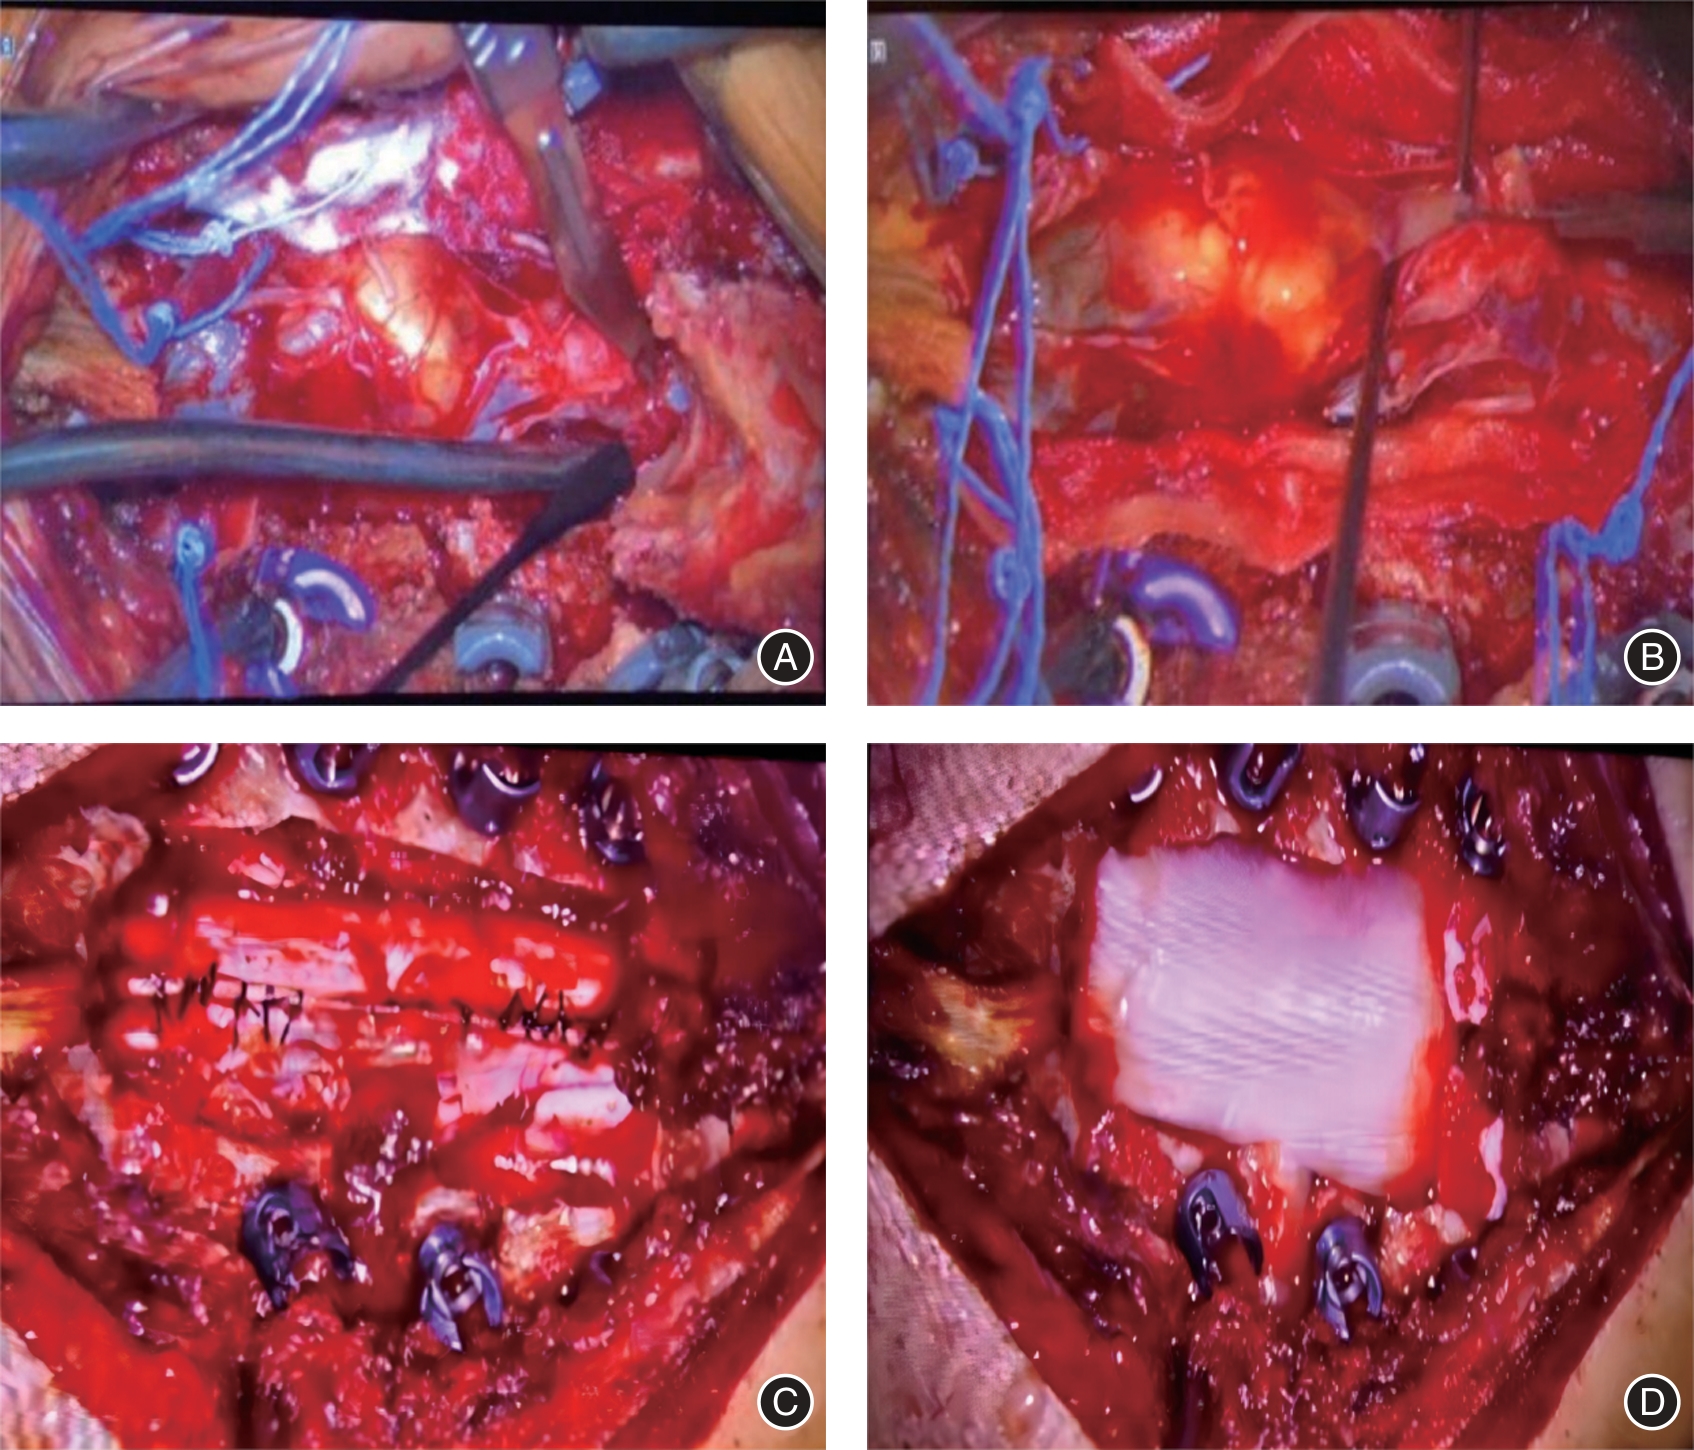

目的 研究用于辅助椎管内肿瘤切除手术的3D显微镜技术对椎管内肿瘤疾病的临床治疗效果与安全性。 方法 分析2019年1月至2023年7月治疗的椎管内肿瘤患者37例,采用3D显微镜下肿瘤切除(3D组)治疗的患者15例,采用普通显微镜下肿瘤切除(普通组)治疗的患者22例。比较两组患者的围术期指标、临床疗效指标、安全性指标。 结果 普通组手术时间(223.78 ± 46.46)min,3D组手术时间(182.93 ± 39.28)min,与普通组相比手术时间明显偏低(P < 0.05),其他围手术期指标两组比较差异无统计学意义(P > 0.05)。所有患者在术后疼痛症状均得到明显减轻,并且在一定程度上恢复了较好神经功能。对比术前,两组患者术后24 h以及术后1年的VAS评分,差异有统计学意义(P < 0.01),组间比较差异无统计学意义(P > 0.05), McCormick脊髓功能评级在术后1年均为Ⅰ级。两组术后并发症发生率差异无统计学意义。 结论 使用3D显微镜技术与普通显微镜技术进行椎管内肿瘤手术均具有较好的临床疗效。但于3D显微镜下能明显缩短手术时间,以此降低手术并发症的风险,具有更优的临床安全性。

Objective To investigate the clinical treatment effect and safety of 3D microscopy technology for adjuvant neuraxial tumor resection on neuraxial tumor diseases. Methods A total of 37 patients with neuraxial tumors treated from January 2019 to July 2023, 15 patients treated with 3D microscope tumor resection (3D group), and 22 patients treated with general microscope tumor resection (ordinary group) were analyzed. The perioperative indexes, clinical efficacy indexes and safety indexes were compared between the two groups. Results The operation time was (223.78 ± 46.46) min in the ordinary group and (182.93 ± 39.28) min in the 3D group, which was significantly lower than that in the ordinary group (P < 0.05), and there was no significant difference in other perioperative indicators between the two groups (P > 0.05). All patients had significantly reduced their postoperative pain symptoms and recovered their neurological function to a certain extent. There were statistically significant differences between the two groups (P < 0.01), but there was no statistical difference between the two groups (P > 0.05), and the McCormick spinal cord function rating was grade I. at one year after surgery. Conclusion The use of 3D microscopy and general microscopy for neuraxial tumor surgery has good clinical efficacy. However, the operation time can be significantly shortened under 3D microscopy, thereby reducing the risk of surgical complications and has better clinical safety.